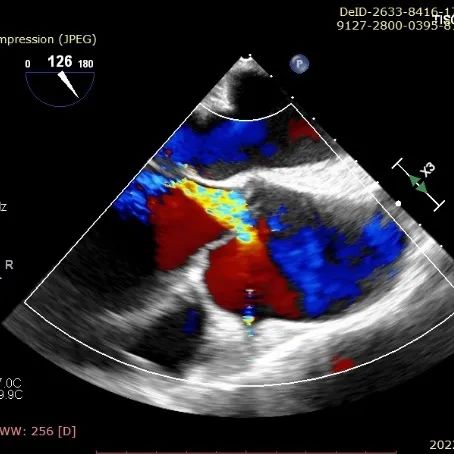

TEE示主动脉瓣大量反流

DSA(左)及TEE(右)提示无瓣周漏